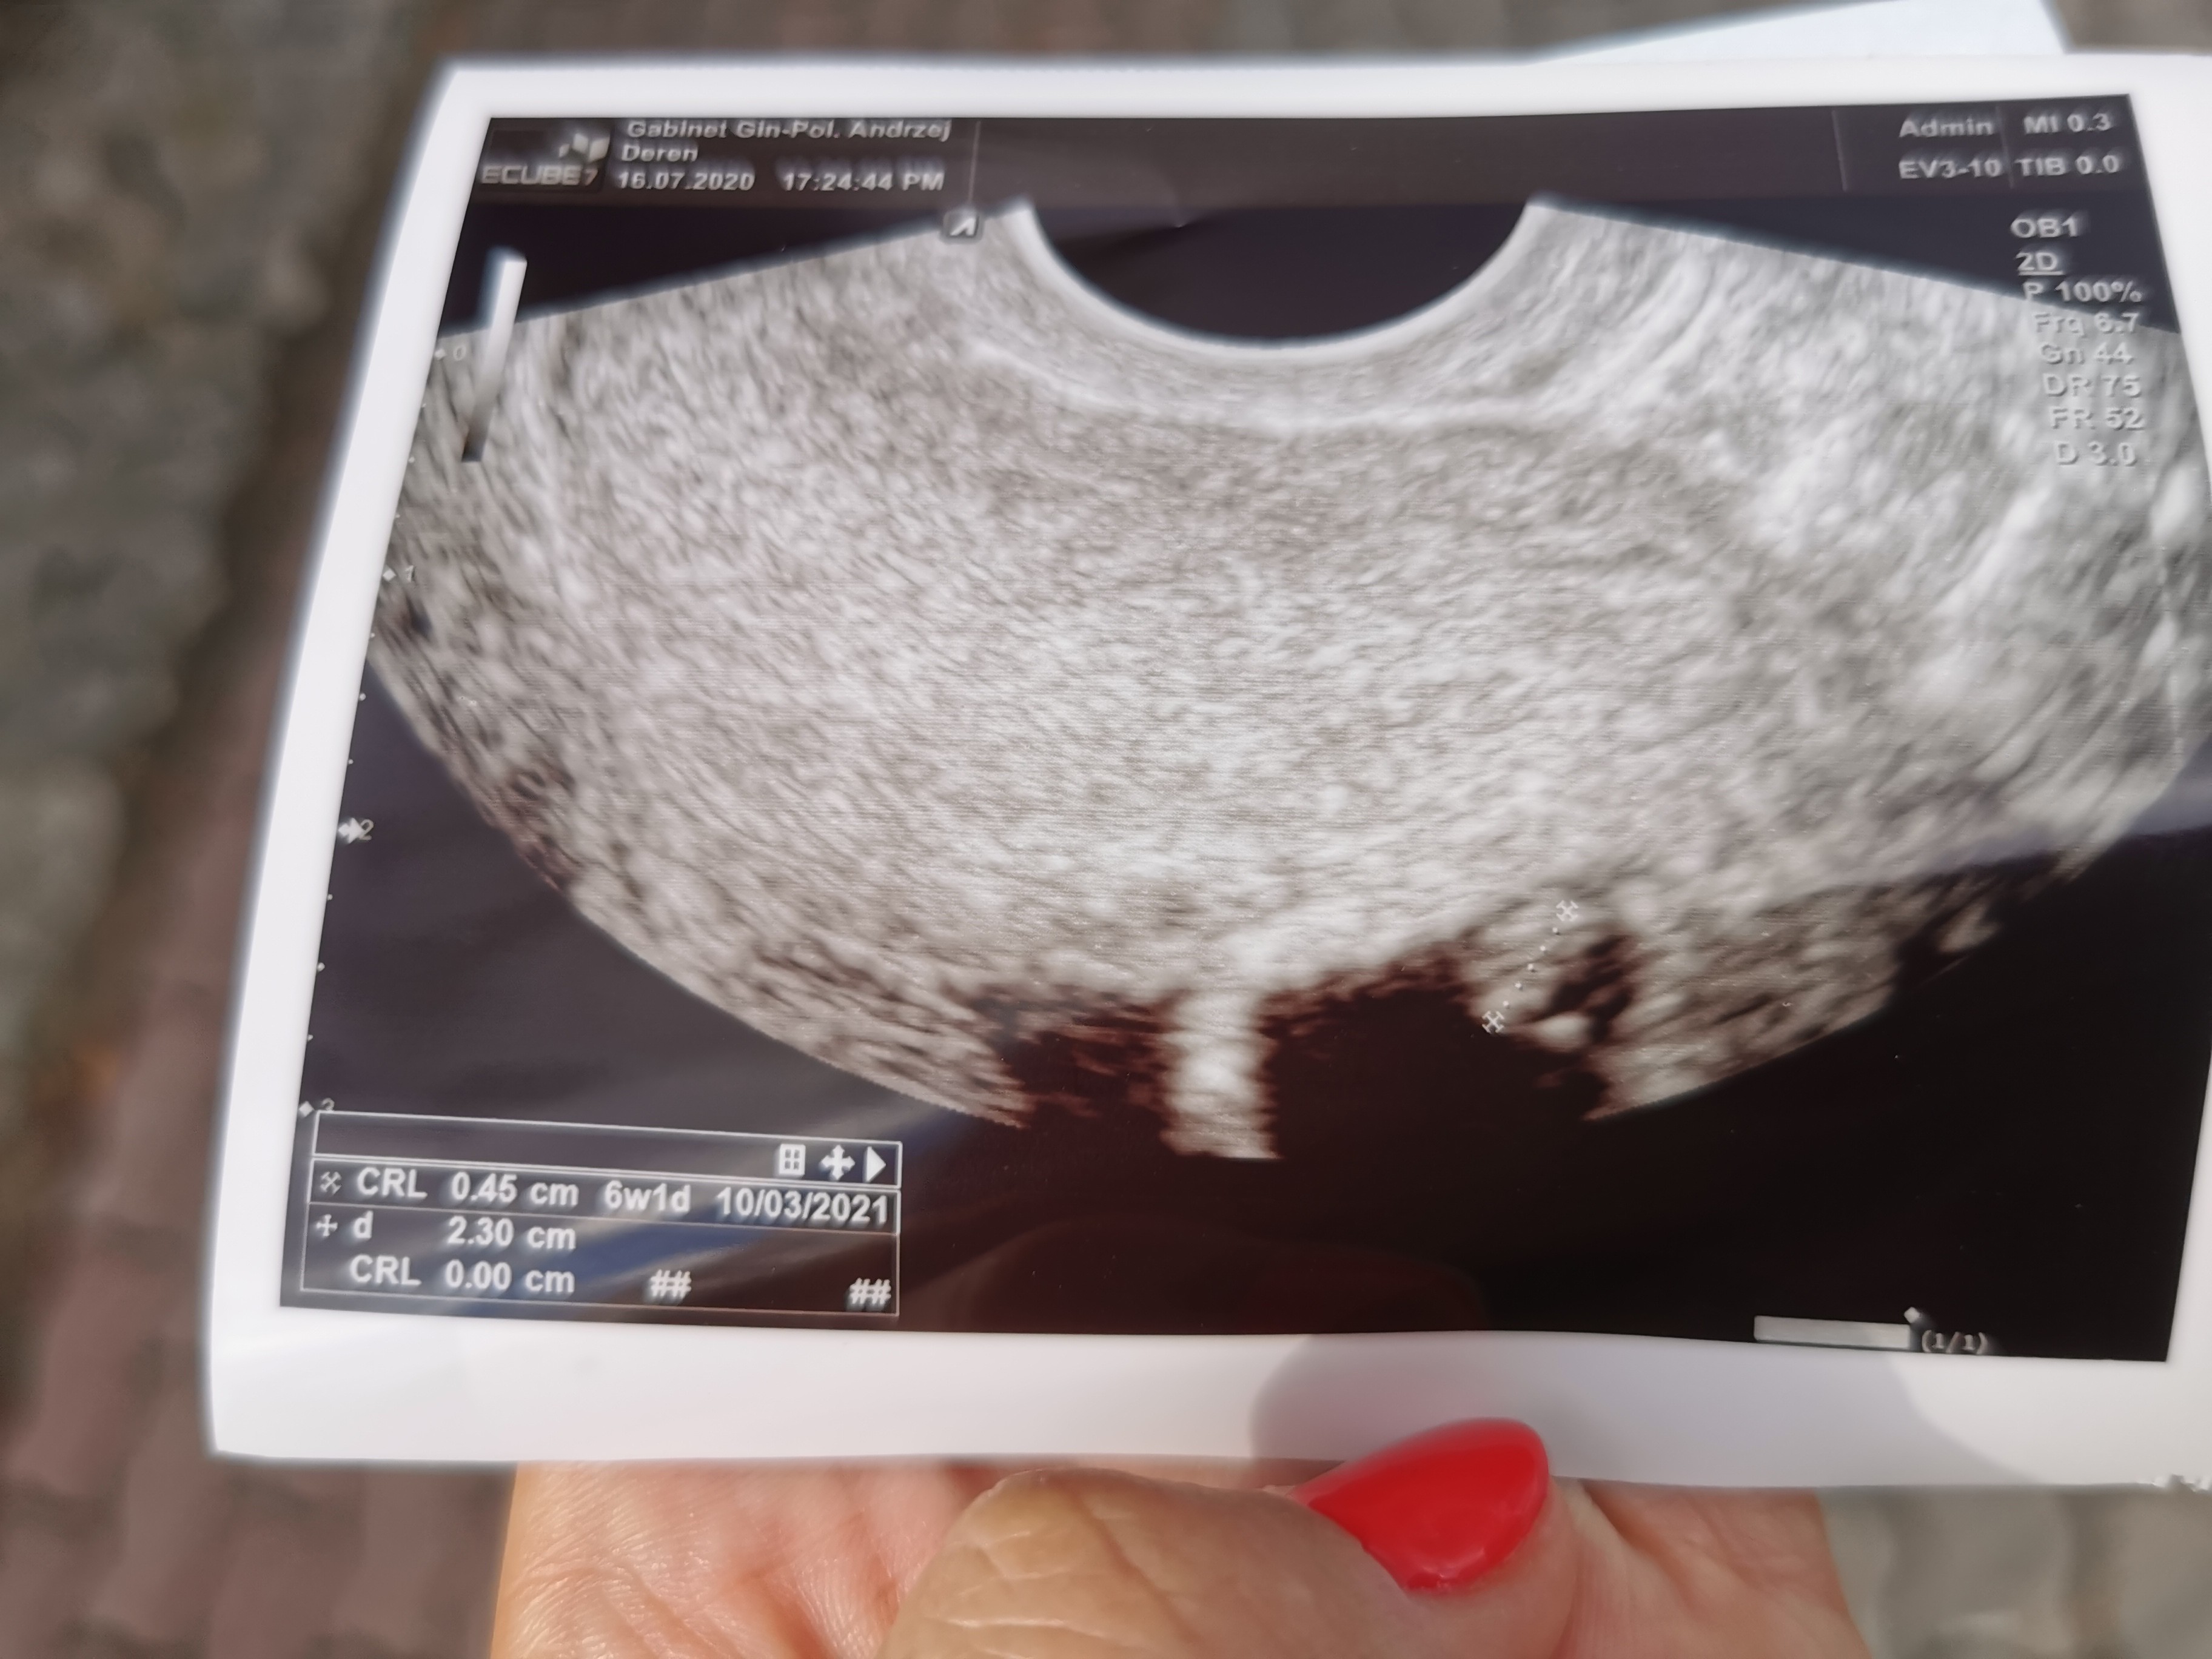

Jestem po wizycie.. Wg OM 7tc 3d wg USG 6tc 1d. Żeby tego było mało, lekarz wogole mnie nastraszył, że jakbym krwawiła to mam jechać do szpitala.. I że teraz jest dużo poronień. I mam przyjechać za tydzien zobaczyć czy bije serduszko. Wogole jestem na niego wkurzona.. Jak robił usg widziałam na własne oczy że bije serce, a on to jest jeszcze za mloda ciąża.. Wogole nie dało się z nim porozmawiać. Dał mi jakiej byle jakie zdjęcie. Prowadziłam u niego druga ciąże i jestem w szoku. Wstawiam zdjęcie, dziewczyny nie sądzicie ze on źle zmierzył zarodek?

Trochę Cię zbyl ten lekarz ale ma rację że teraz dużo poronien i trzeba szybko reagować. Ja w 15tyg dostałam krwotoku z dróg rodnych i myślałam że już koniec ale od razu do szpitala pojechałam i dali kroplowki i leki na zatrzymanie krwawienia i wszystko się dobrze skończyło.Jestem po wizycie.. Wg OM 7tc 3d wg USG 6tc 1d. Żeby tego było mało, lekarz wogole mnie nastraszył, że jakbym krwawiła to mam jechać do szpitala.. I że teraz jest dużo poronień. I mam przyjechać za tydzien zobaczyć czy bije serduszko. Wogole jestem na niego wkurzona.. Jak robił usg widziałam na własne oczy że bije serce, a on to jest jeszcze za mloda ciąża.. Wogole nie dało się z nim porozmawiać. Dał mi jakiej byle jakie zdjęcie. Prowadziłam u niego druga ciąże i jestem w szoku. Wstawiam zdjęcie, dziewczyny nie sądzicie ze on źle zmierzył zarodek?